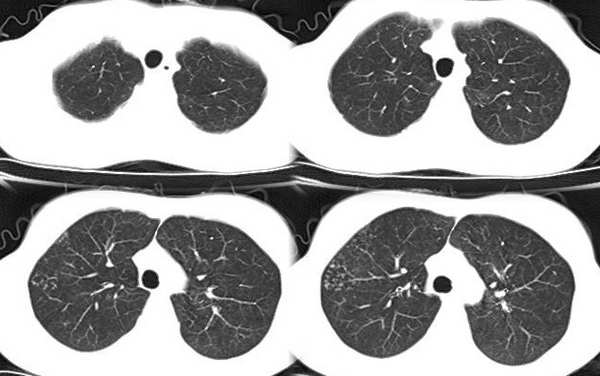

以下是引用x线在2006-2-2 17:37:00的发言:[br]结合病史支持“ct拟诊:双侧tb,左下叶结核球,左下叶局限性轻度支扩。”双下叶及左舌叶淡薄的毛玻璃密度影,我考虑为炎性渗出。另:是否合并霉菌感染须进一步检查确定。